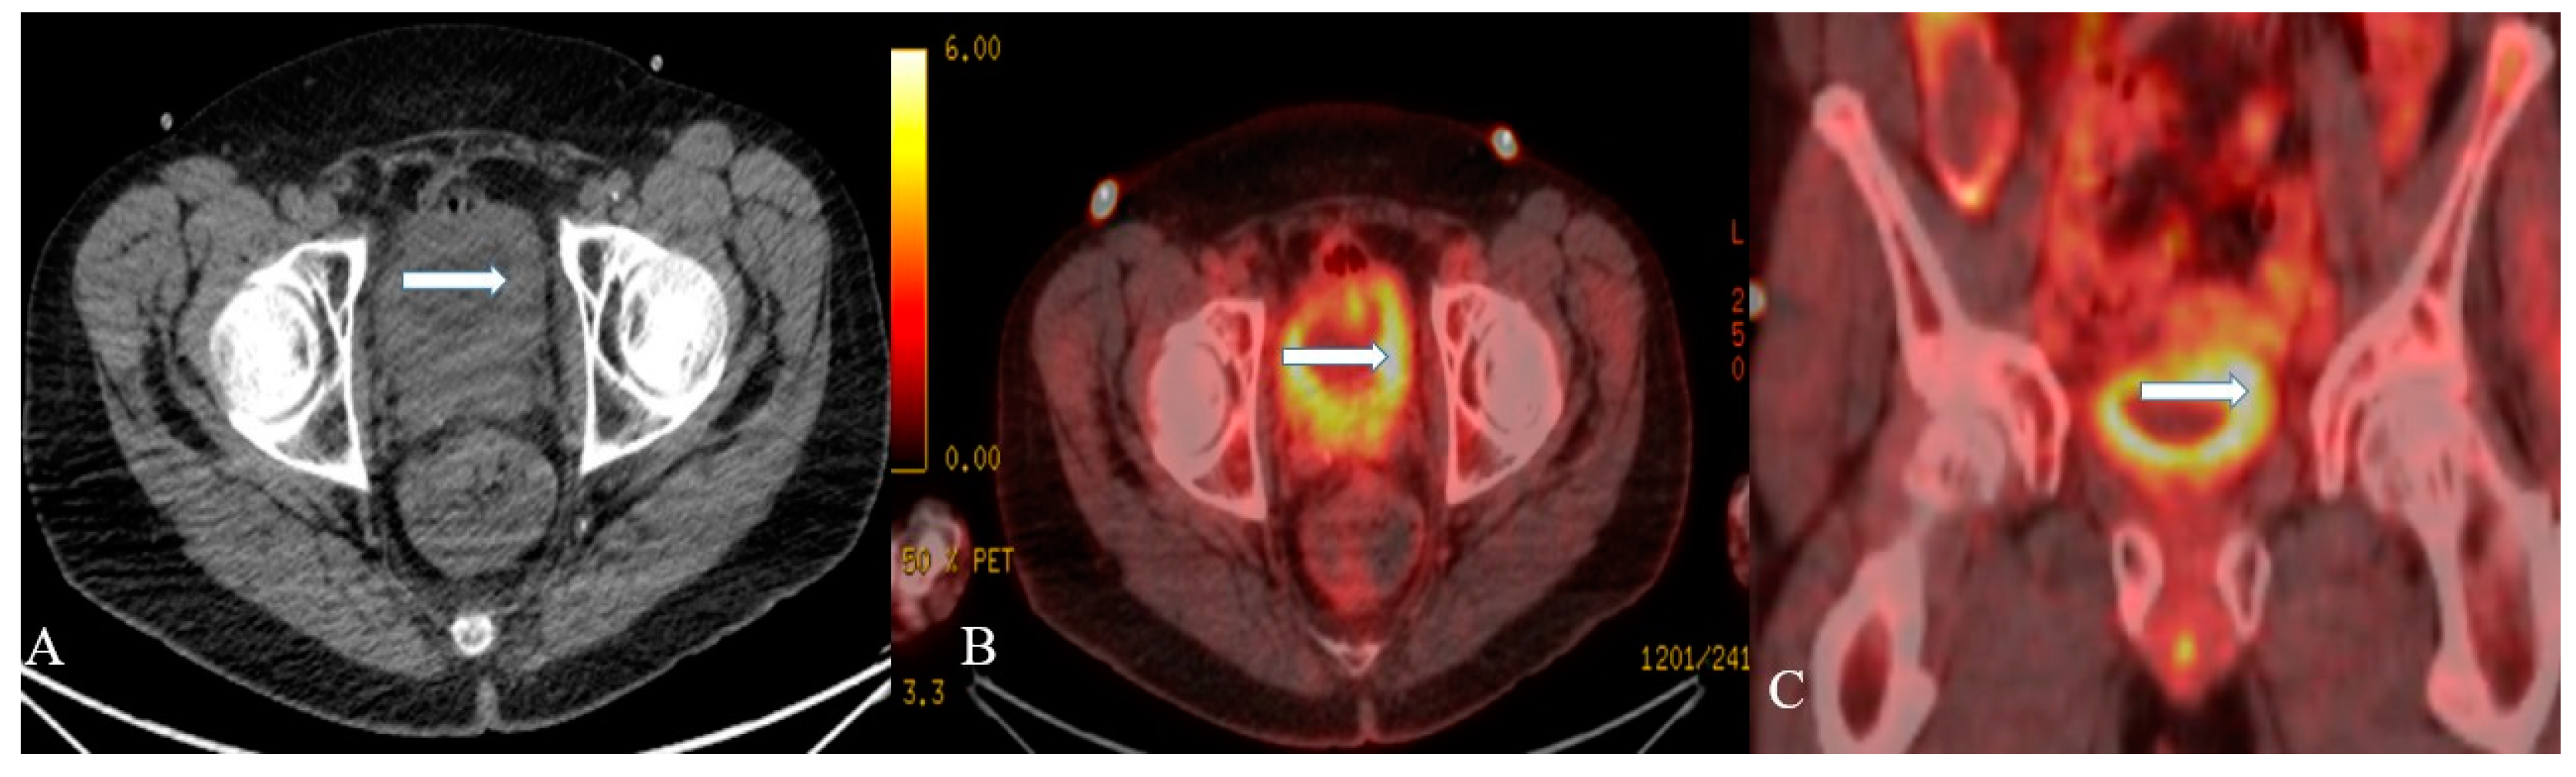

3.2. Imaging

- Hwang, J.J.; Uchio, E.M.; Patel, S.V.; Linehan, W.M.; Walther, M.M.; Pacak, K. Diagnostic localization of malignant bladder pheochromocytoma using 6-18F fluorodopamine positron emission tomography. J. Urol. 2003, 169, 274–275. [Google Scholar] [CrossRef]

- Halefoglu, A.M.; Miroglu, C.; Uysal, V.; Mahmutoglu, A. Malignant paraganglioma of the urinary bladder. Eur. J. Radiol. Extra 2006, 58, 53–58. [Google Scholar] [CrossRef]